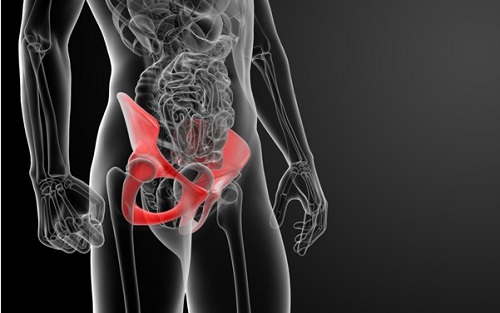

고관절이란

고관절은 흔히 엉덩이 관절이라고 불리며, 골반 쪽에 위치한 공-소켓(ball-and-socket) 형태의 관절입니다. 둥근 모양의 대퇴골두가 오목한 비구(acetabulum)에 맞물려 있어 골반과 허벅지를 연결하는 역할을 합니다.

이 관절은 체중을 지탱하고 보행, 달리기 같은 다리의 움직임을 가능하게 하는 핵심 구조입니다.